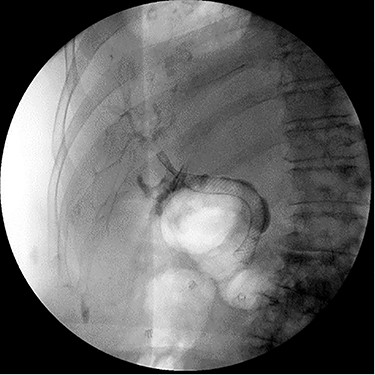

On 5-day follow-up, the JP drainage was nonbilious and the drain was removed. On removal, the metal stent was also explanted. The stent was found to have been inadvertently deployed through a side fenestration of the JP drain lumen (Fig. 3).

Explanted metal biliary stent deployed through surgical drain lumen.